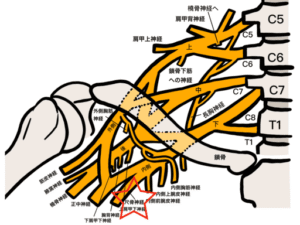

②尺骨神経の治療

正中神経は頚椎(首の骨)からはじまります

そのため首の治療をすることで

正中神経の圧迫がとれるので必須の治療になります

神経圧迫がとれることで

手首まわりに栄養が届きやすくなります

首の治療では正しいところに針があたると

小指側の前腕や手首のあたりに響きがあります